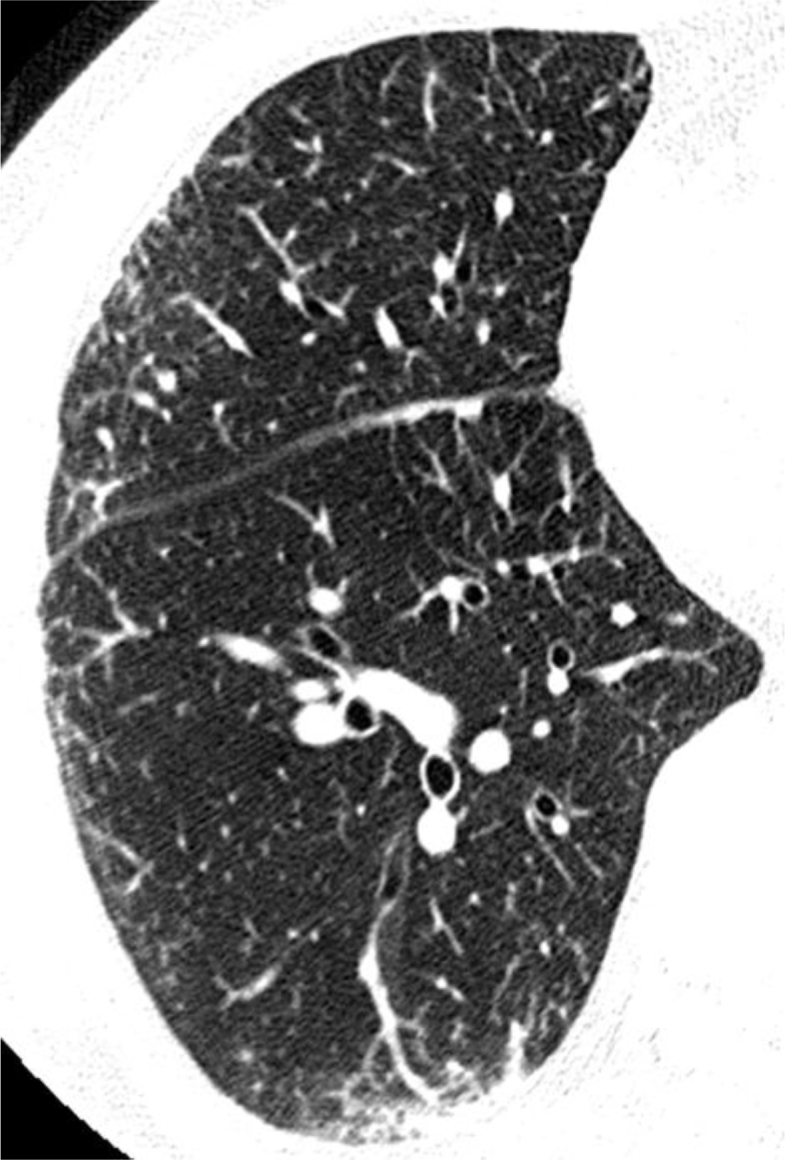

Fig. 2.

High-resolution computed tomography showed bilateral ground glass opacities and septal line thickenings with subpleural distribution in the middle and lower lobes.

Pietra and coworkers indicated that drug-induced eosinophilic lung disease has two patterns; acute and chronic form [4]. It was also reported that the opacities of chronic patterns were persistent despite the cessation of causative agents and the administration of oral prednisolone [5], [6]. In this case, clinical symptoms appeared after prescribing camostat mesilate for ten days. HRCT findings showed mainly GGO and septal line thickening with subpleural distribution in the middle and lower lobes. Dominant histological findings are characterized by accumulations of eosinophils and macrophages and infiltrations of eosinophis, lymphocytes and plasma cells in the alveolar septa. All these findings are consistent with acute form. Indeed, the clinical condition of the present case was improved only by the cessation of camostat mesilate. Therefore, we speculate that early diagnosis and therapeutic intervention are very important for favorable outcome.